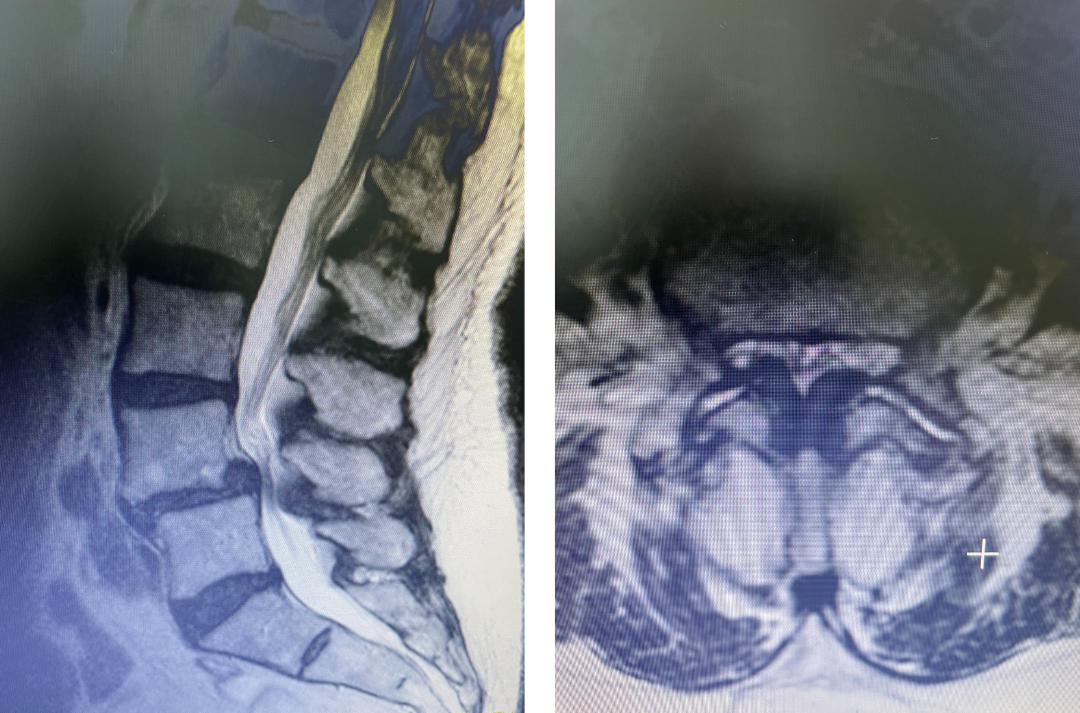

Figure 1. Sagittal and axial T2-weighted MRI of the spine demonstrating severe next segment stenosis above the prior fusion worse at L3-4 mainly due to severe ligamentous hypertrophy

This next patient was a 54-year-old female who had a long history of low back pain with radiation to both legs. She had a prior L4-S1 instrumented fusion and a L3-S1 laminectomy two years prior. In the past six months she has developed worsening low back pain and bilateral leg radiation. She had tried medications, epidurals, and PT but with no improvement. Imaging revealed severe stenosis above her prior fusion at L3-4 secondary to thickened ligament and facet hypertrophy or enlargement. This was also evident slightly less so at L2-3 (Fig 1). This ligament is in particular commonly involved in causing lumbar stenosis. This is a ligament that looks yellow in the operating room for which its purpose normally is to act like a rubber band to limit extremes of flexion and to aid in upright posture. Perhaps this ligament thickens to compensate for the decrease in upright support as we get older. It was decided initially to perform an L2-4 revision laminectomy, explore the prior fusion, and remove the hardware. We would leave the L4 screws in and add screws at L2 and L3, giving her a shorter segment of fusion mass if she was indeed fully fused.